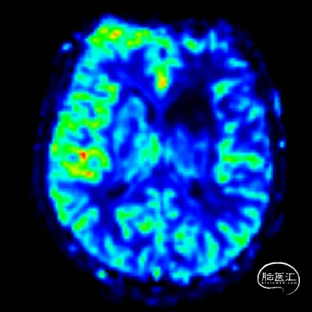

术前DSA造影显示左侧颈内动脉自起始段闭塞,C6眼段以上供血区由颈外动脉眼动脉反向代偿供血,左侧大脑中动脉供血区由前交通动脉代偿供血。

· 术前影像提示左侧颈内动脉自起始段闭塞,结合患者右侧肢体乏力、失语等症状,明确此处为责任血管。结合高分辨核磁的斑块分析,考虑到闭塞段可能存在不稳定斑块或新鲜血栓,术中操作易引发远端栓塞,故采用COSIS技术(颅内取栓支架保护下的慢闭开通术)。